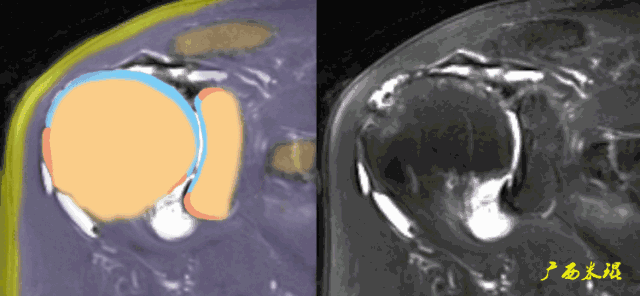

3、轴位:平行于关节盂/垂直于盂肱关节,主要评估盂唇,同时兼顾肩胛下肌、冈下肌及小圆肌。

各个序列肩袖均表现为均匀的低信号,是肌腱的延续。